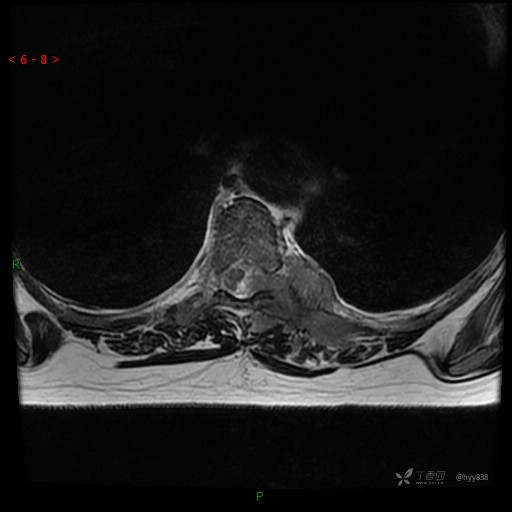

MRI AXI T2WI